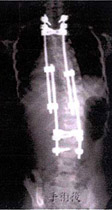

(a)手術前   (b)手術後

???????????????????????????????????????                                       (幼児の側弯症)

(注) 非観血治療としての保存療法を試すことなく、すぐ手術すると、この先成長が止まるまで年に数回入院し金具を伸ばさないと身長が伸びなくなる。

どちらを選ぶかは医師の診断ですが、まずは保存療法を選ぶことも選択肢の一つです。

幼児の体への負担は明白です。